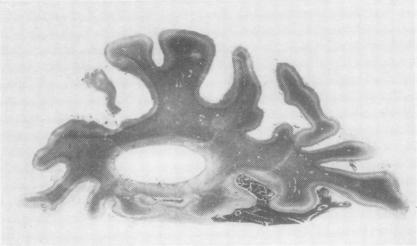

A case of lipoidosis following Rh factor incompatibility.

J Clin Pathol. 1956 Nov;9(4):326-32. doi: 10.1136/jcp.9.4.326.